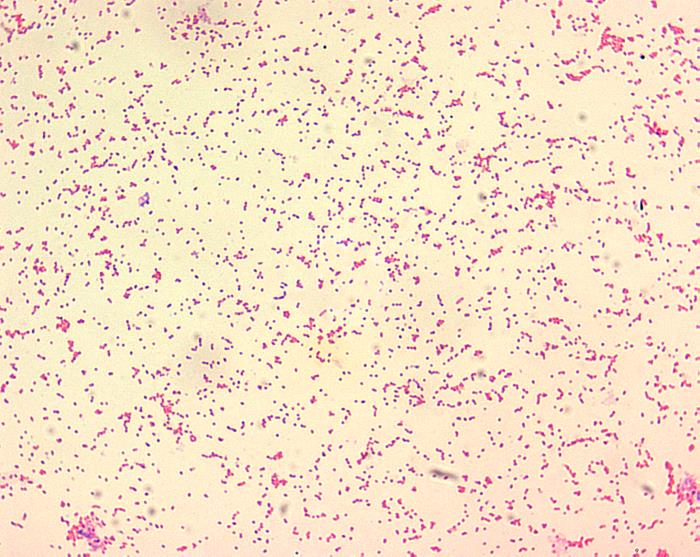

布魯氏桿菌是一種革蘭氏陰性的不運(yùn)動(dòng)細(xì)菌,它會(huì)引起布魯氏桿菌病,它是一種人畜共患的慢性傳染性疾病,危害大。在我國(guó)該疾病的主要傳染源來(lái)自牛、羊、豬3種牲畜。如何鑒別布魯氏桿菌呢?生物顯微鏡在這里起到大作用。

布魯氏菌在生物顯微鏡下通常呈球形、球桿形或短桿形,菌體大小一般在0.5~0.7μm×0.6~1.5μm之間。無(wú)芽胞、無(wú)鞭毛,且常單個(gè)存在,很少成雙、短鏈或小堆狀排列。

經(jīng)過(guò)吉姆薩染色呈紫紅色